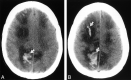

fig. 4. CT scans obtained at the time of toxic reaction shows areas of low attenuation extending centrally from the frontal lobe to the parietal region, involving the white matter and projecting to the cortical surface. Hemorrhages are noted in the right frontal lobe and right parietal area (arrows). The brain abnormalities are severe and appear to lie in a region that could easily coincide with the boundary between anterior cerebral and middle cerebral territories. Images were obtained in a patient (case 11), conditioned for transplantation with cyclophosphamide and busulfan, who presented with generalized tonic-clonic seizure activity 8 d after transplantation. At the onset of toxic reaction, the patient had grade 3 BMT-related TM that rapidly worsened to grade 4. The cyclosporin level at the time of toxic reaction was within the normal therapeutic range. Her baseline blood pressure was 110/70 mm Hg, which increased to 152/96 mm Hg at toxic reaction